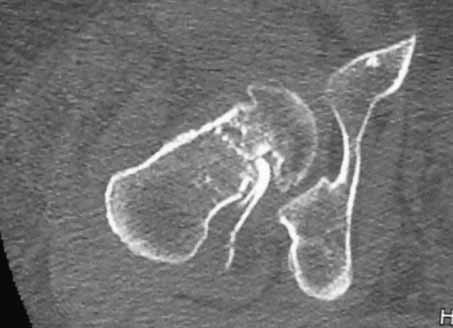

Пациентка 53 лет. ДТП 09.01.12: сочетанная травма: перелом 2-5 ребер справа, ушиб легких;

перелом обеих лонных костей без смещения; закрытый перелом проксимального конца правой

бедренной кости; открытый оскольчатый внутрисуставной перелом проксимальных концов

костей правой голени.

Бедро одномоментно делать не стал, не было уверенности в наличии перелома на уровне шейки. Во время операции смотрел тазобедренный сустав под ЭОПом,

головка неподвижна. После операции повторили КТ, стало очевидно, что имеется субкапитальный перелом. Что делать, остесинтез или протезирование? Если остеосинтез, то чем? Заранее благодарен за советы.